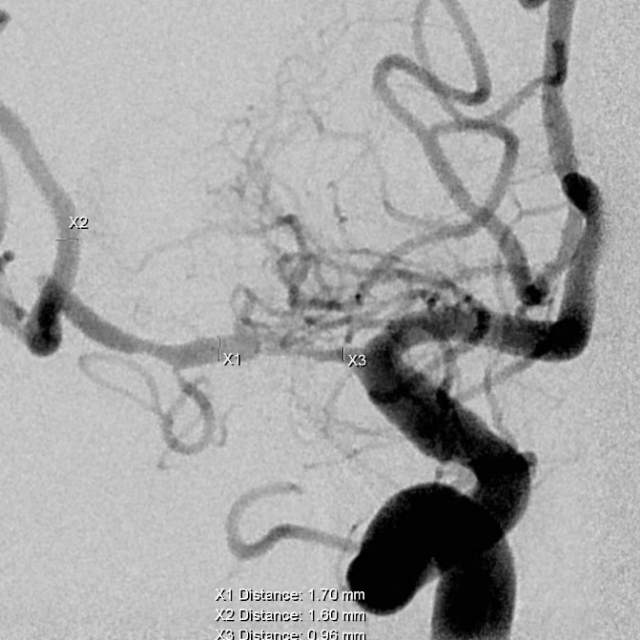

1、第一个患者:我们给予一期外科干预后,一个月后检查发现,狭窄的部位比术后即刻有改善,继续药物治疗,暂时无需手术,出院继续随访;

术前

术后即刻

一个月后随访好转,继续观察